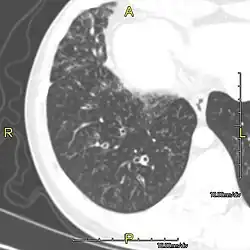

Around 80% of people with primary ciliary dyskinesia experience respiratory problems beginning within a day of birth. Many have a collapsed lobe of the lung and blood oxygen low enough to require treatment with supplemental oxygen.[1] Within the first few months of life, most develop a chronic mucus-producing cough and runny nose.[1] The main consequence of impaired ciliary function is reduced or absent mucus clearance from the lungs, and susceptibility to chronic recurrent respiratory infections, including sinusitis, bronchitis, pneumonia, and otitis media. Progressive damage to the respiratory system is common, including progressive bronchiectasis beginning in early childhood, and sinus disease (sometimes becoming severe in adults). However, diagnosis is often missed early in life despite the characteristic signs and symptoms.[2] In males, immotility of sperm can lead to infertility, although conception remains possible through the use of in vitro fertilization, there also are reported cases where sperm were able to move.[8] Trials have also shown that there is a marked reduction in fertility in females with Kartagener's syndrome due to dysfunction of the oviductal cilia.[9]

Many affected individuals experience hearing loss and show symptoms of otitis media which demonstrates variable responsiveness to the insertion of myringotomy tubes or grommets. Some patients have a poor sense of smell, which is believed to accompany high mucus production in the sinuses (although others report normal – or even acute – sensitivity to smell and taste). Clinical progression of the disease is variable, with lung transplantation required in severe cases. Susceptibility to infections can be drastically reduced by an early diagnosis. Treatment with various chest physiotherapy techniques has been observed to reduce the incidence of lung infection and to slow the progression of bronchiectasis dramatically. Aggressive treatment of sinus disease beginning at an early age is believed to slow long-term sinus damage (although this has not yet been adequately documented). Aggressive measures to enhance clearance of mucus, prevent respiratory infections, and treat bacterial superinfections have been observed to slow lung-disease progression. The predicted incidence is 1 in approximately 7500.[10]

Diagnosis

Several diagnostic tests for this condition have been proposed.[5] These include nasal nitric oxide levels as a screening test, light microscopy of biopsies for ciliary beat pattern and frequency and electron microscopic examination of dynein arms, as the definite diagnosis method. Genetic testing has also been proposed but this is difficult given that there are multiple genes involved.[6]